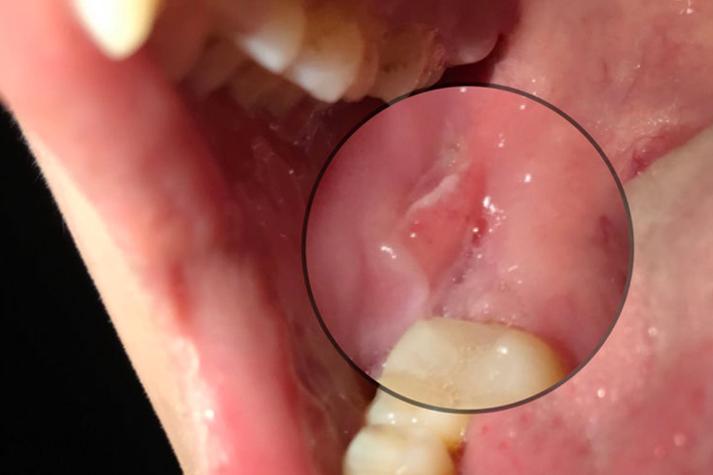

- 特点: “红、黄、凹、痛”,溃疡面周围有红晕,中心覆盖黄色假膜,凹陷,疼痛明显。

- 尺寸: 直径通常小于5毫米。

- 病程: 7-10天自愈,不留疤痕。

- 频率: 每年发作数次。